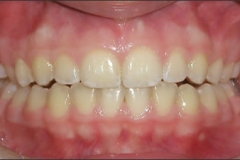

This young patient was self-conscious about the appearance of her short teeth and gummy smile. Through crown lengthening and tooth whitening procedures, we were able to create a beautiful, more mature smile.

Click on a thumbnail to view the before and after photos.